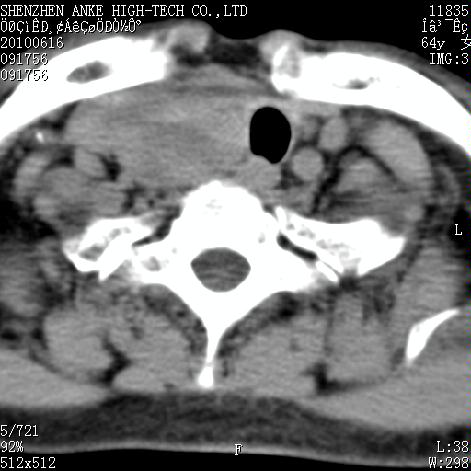

标题: CT27132:患者女,64岁,颈部及全身多处包块,现觉吞咽困难4 [打印本页]

标题: CT27132:患者女,64岁,颈部及全身多处包块,现觉吞咽困难4

右侧甲状腺占位,肿瘤可能性大,癌

右侧甲状腺癌伴右颌下腺淋巴结转移

右侧甲状腺癌伴淋巴结转移

右侧甲状腺癌伴淋巴结转移可能性大

右侧甲状腺癌伴淋巴结转移可能性大。